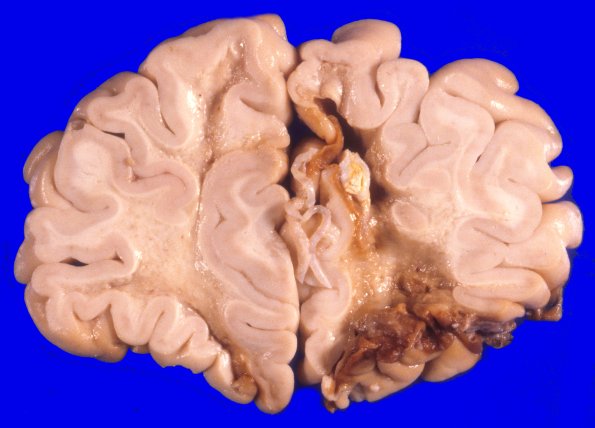

17A4 Trauma, Baseball bat (Case 17) 3

Multiple coronal sections demonstrating many severe contusive injuries with underlying loss of white matter.